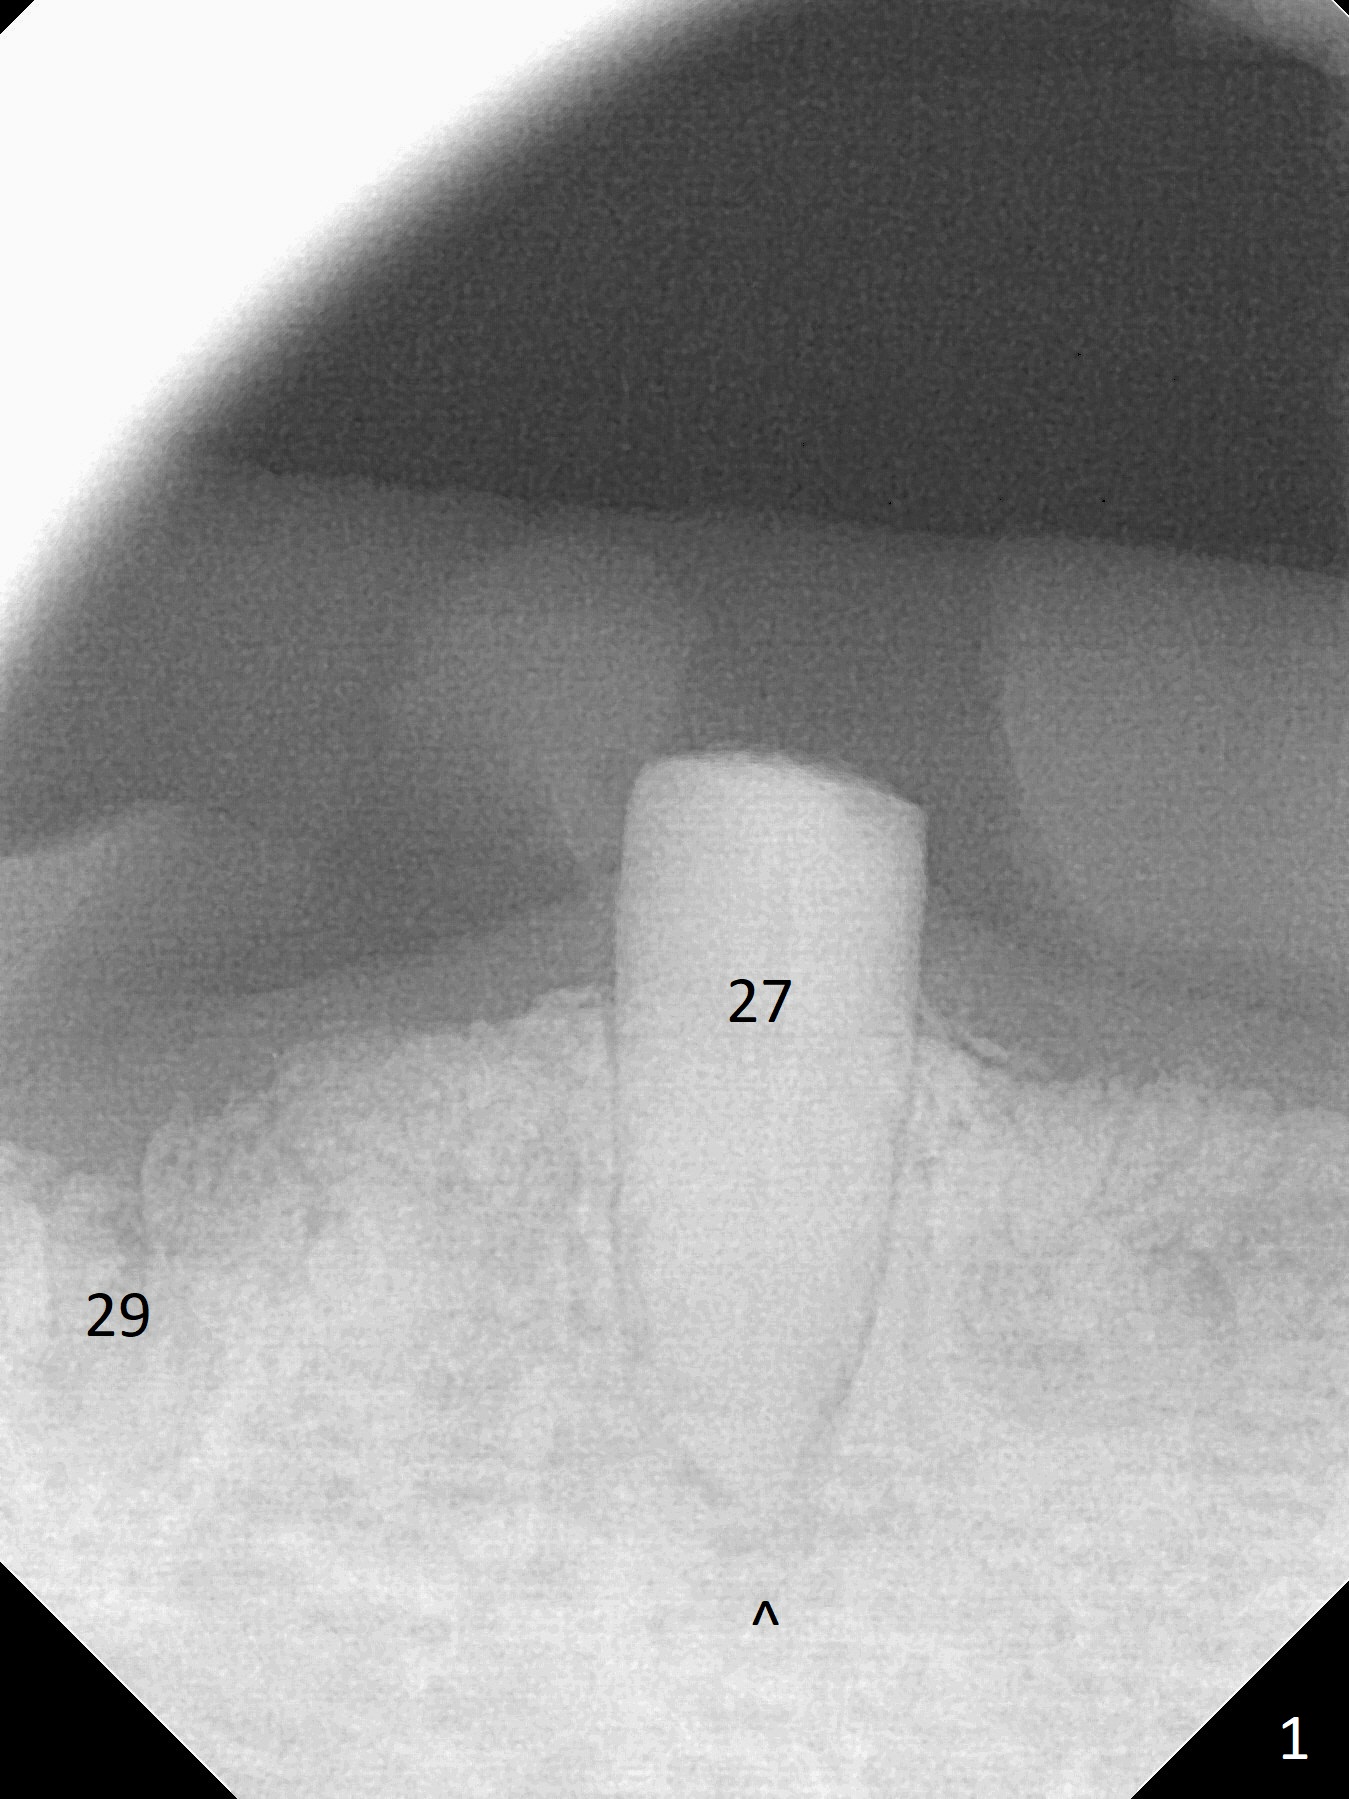

A 79-year-old woman with osteoporosis has a lower RPD, which becomes loose when #29 was extracted a few months earlier. The tooth #22 has mobility II (Fig.2 (increased pdl)), while the tooth #27 is short with periapical radiolucency (Fig.1,3 ^). The latter needs RCT and crown. For #29 implant placement, osteotomy should be underprep: 2 mm drill for 12 mm for 10 mm long implant (2 mm gingiva), 2.7 mm for 8 mm (Fig.3,4 (low bone density)).